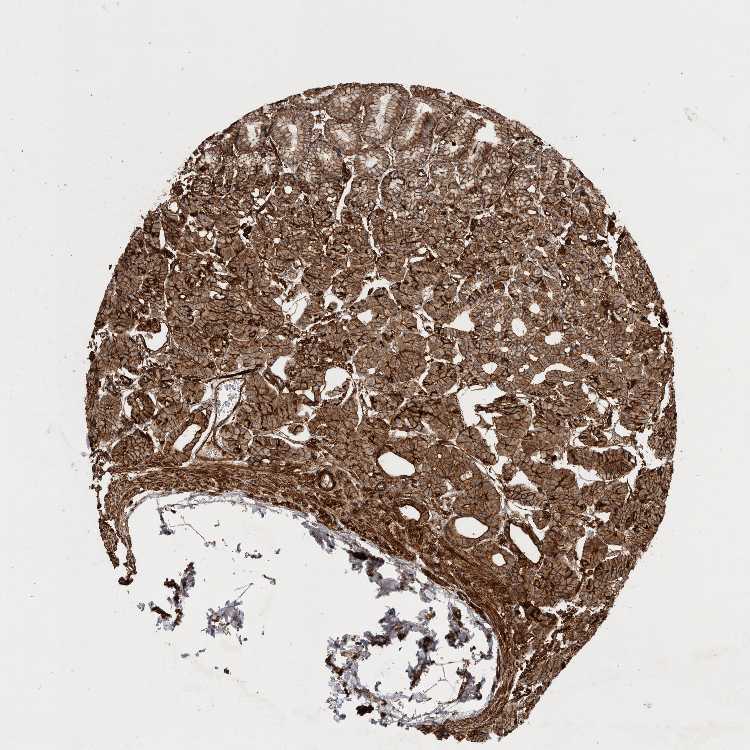

STOMACH 1 - Antibody stainingi

Antibody staining in the annotated cell types in the current human tissue is reported as not detected, low, medium, or high, based on conventional immunohistochemistry profiling in selected tissues. This score is based on the combination of the staining intensity and fraction of stained cells.

Each image is clickable and will lead to virtual microscopy that enables deeper exploration of all samples and also displays staining intensity scores, fraction scores and subcellular localization as well as patient and tissue information for each sample.

Antibody HPA027052

Glandular cells High